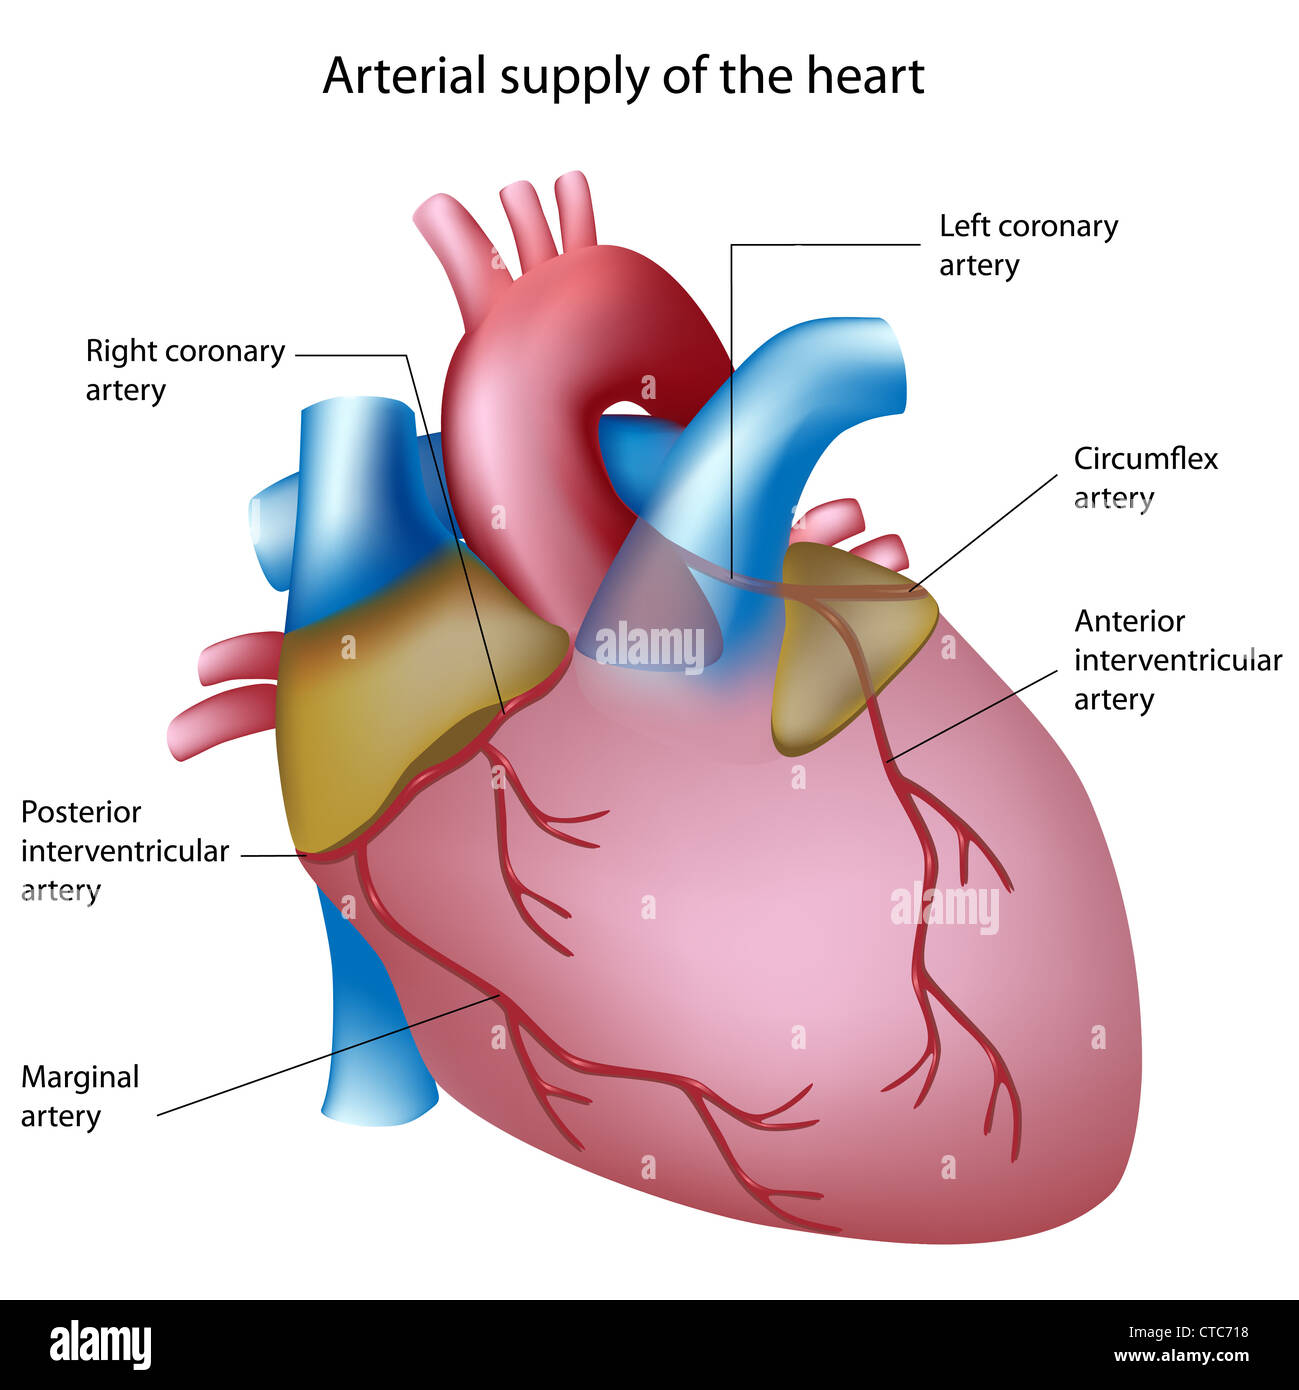

Coronary arteries Stock Photohttps://www.alamy.com/image-license-details/?v=1https://www.alamy.com/stock-photo-coronary-arteries-49441428.html

Coronary arteries Stock Photohttps://www.alamy.com/image-license-details/?v=1https://www.alamy.com/stock-photo-coronary-arteries-49441428.htmlRFCTC718–Coronary arteries